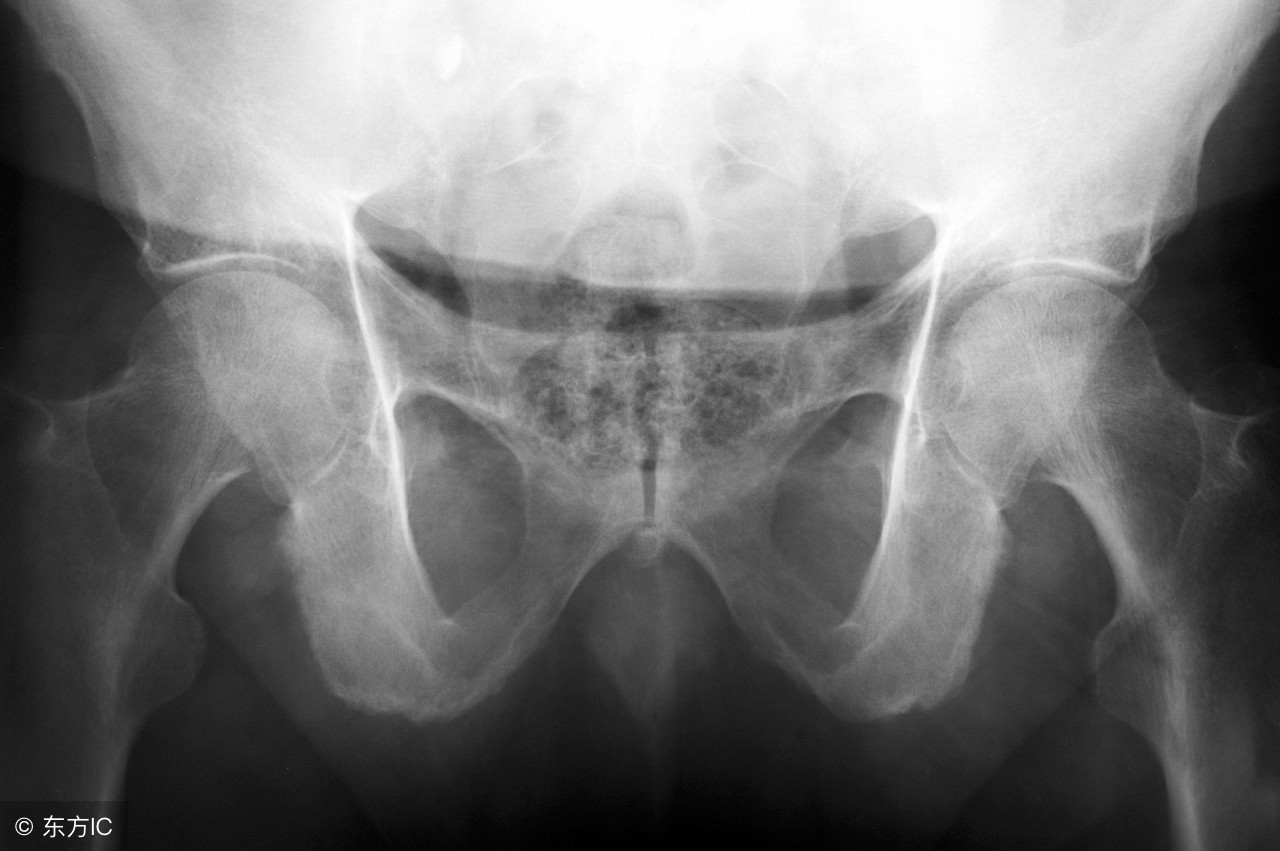

据沈慧勇教授及其团队诊断,小陈是得了强直性脊柱炎。其实,小陈的病情属于严重一类,常规治疗效果欠佳,但如若使用已上市的生物制剂,小陈的家庭经济又无法负担。

据沈慧勇教授介绍,类似于小陈这种病例并不少见,很多病人被误诊误治多年后才被最终确诊。但是,强直性脊柱炎发病机制尚不清楚,治疗方式非常棘手,至今还未有治愈的办法,在民间被称为“不死的癌症”。